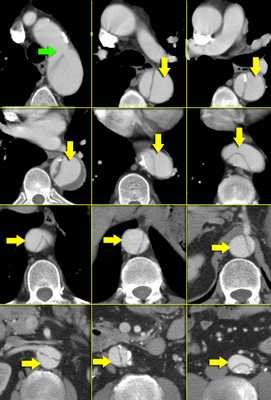

Радиологические находки

- На ниже лежащих снимках представлен пациент с диссекцией типом B. Истинный просвет окружен кальцификацией. Истинный просвет узкий и подвергается компрессионным изменениям, обусловленных систолическим давлением.

- При диссекции аорты интима визуализируется по старым данным только в 70% случаев, но связи с развитием техники данный показатель на сегодняшний день составляет выше 90%.

- На ниже представленных изображениях представлена диссекция типа B.

- Истинный просвет, окружен кальцификатами.

- Истинный просвет уже, чем ложный просвет, а также четко визуализируется симптом клюва.

- В ложном просвете локализован тромб, который контрастируется позже истинного просвета.

Истинный просвет

- Как правило:

- Окружен кальцификацией.

- Меньше, чем ложный просвет.

- Частая локализация чревный ствол, передняя мезентариальная артерия и правая почечная артерия.

Ложный просвет

- Есть окклюзия тромбом или нет.

- Замедленное контрастирование.

- Шире, чем истинный просвет.

- Имеет круговую конфигурацию

- Симптом клюва.

- Окружает истинный просвет при диссекции типа А

- Ниже представлена диссекция, при которой ложный просвет шире истинного.

- Истинный просвет уже и визуализируется более ярче при сравнении с ложным.

- В ложном просвете есть процесс тромбообразование.

- Истинный просвет обычно уже ложного, а также всегда вокруг истинного просвет возможно определить клинья, что является следствием постоянного систолического давления.

- В данном случае представлено типичное прилежания ложного просвета к наружной кривизне дуги аорты.